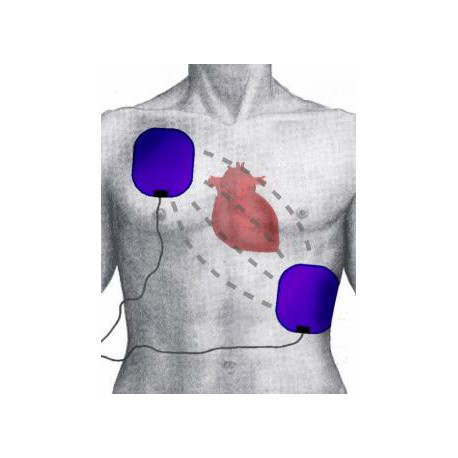

Adaptateurs externes (bandes adhésives en aluminium) pour défibrillateurs de formation Philips HS1 et FRx, permettant d’établir le contact entre les électrodes sur tout mannequin de RCP lors des simulations.

L’adaptateur externe pour défibrillateur de formation Philips HS1 et FRx est conçu pour simuler efficacement une réanimation cardio-pulmonaire (RCP) sur tout type de mannequin de formation.

Ces bandes adhésives en aluminium assurent le contact entre les deux électrodes lors des exercices pratiques, garantissant une simulation réaliste et conforme aux protocoles de formation.

Cet accessoire est indispensable pour les modèles de formation HS1 (ancien modèle) et FRx, et offre une mise en place rapide et simple sur le torse du mannequin.

Utilisation : Simulation de RCP sur mannequins de formation

Fonction : Établir le contact entre les électrodes de formation